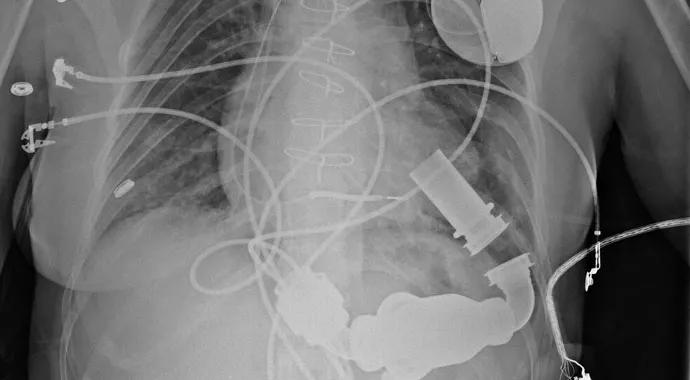

Case Study: Treatment of Postpartum Cardiomyopathy with LVAD and Heart Transplantation

Treating peripartum cardioyopathy with advanced therapies

Presentation

A 27-year-old female, 10-weeks postpartum, with no personal or family history of heart failure, was transferred to Cleveland Clinic in cardiogenic shock, with an ejection fraction (EF) of 10 percent. Four weeks prior, she had developed progressive dyspnea on exertion, orthopnea and right upper quadrant pain. Initially diagnosed with cholecystitis, she became hypotensive during cholecystectomy and could not be extubated. She was transferred to another hospital, where she was started on Milrinone and an intra-aortic balloon pump (IABP) was placed before being transferred to Cleveland Clinic.

Evaluation

Upon her arrival in our Heart Failure Intensive Care Unit, her medications were adjusted, and she was extubated. Echocardiogram showed a mildly dilated left ventricle and good right-ventricle function. IABP was removed as it was ineffective in this case, and an Impella was placed with resolution of acute kidney and liver injuries and improvement of cardiac output.

Treatment

Because of the patient’s young age and fairly rapid onset of a nonischemic cardiomyopathy, we implanted a HeartMate II LVAD as a bridge to recovery to give her the best chance of reversing her failing heart. Although her post-operative course was complicated, she was eventually discharged home and was able to resume work and motherhood. After one year, her EF had reached only 15-20 percent on small doses of evidence-based medications, which were limited due to relative hypotension. The patient also suffered from a chronic driveline infection on chronic antibiotic therapy. We decided to proceed with listing her for heart transplantation. She received a new heart in December 2013, 18 months after her initial admission, and is doing very well.